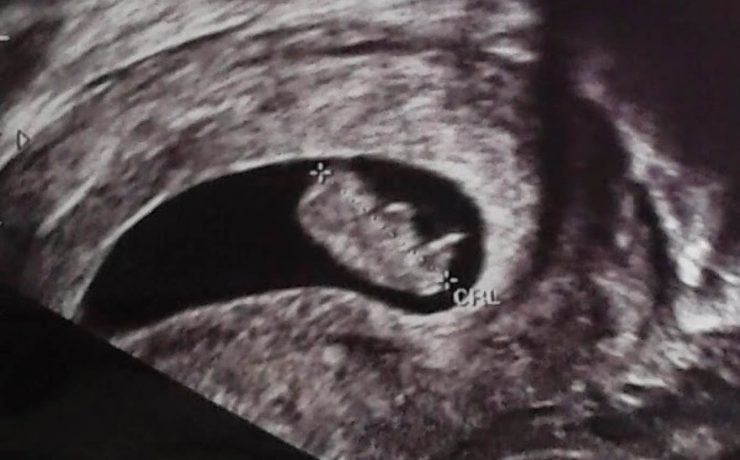

Correlación ultrasonográfica e histopatológica de los tumores de ovario

El cáncer de ovario, constituye el 2 % de las afecciones malignas de la mujer con una alta mortalidad, aproximadamente las dos terceras partes se presentan con lesiones muy avanzadas en el momento del examen imagenológico,1-4 trae por consecuencia una supervivencia menor de la paciente y un aumento del costo